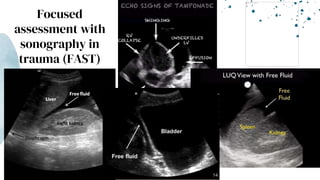

Focused

assessment with

sonography in

trauma (FAST)

Diagnostic peritoneal lavage (DPL)